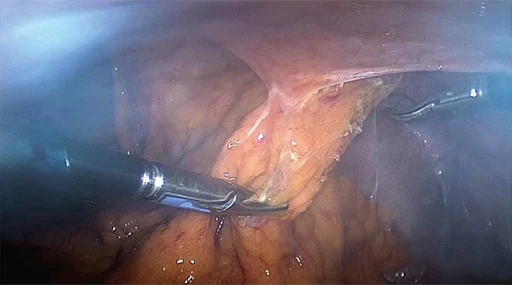

Questa testa telecamera avanzata è dotata della capacità di supportare sia l’imaging a luce bianca che a fluorescenza NIR, consentendo così la visualizzazione in tempo reale delle strutture marcate con ICG. È ideale per procedure oncologiche e vascolari in cui è essenziale una migliore differenziazione dei tessuti.

Doppia modalità di imaging per la precisionechirurgica

Il controller AlphaSMART Cam+ consente di passare senza soluzione di continuità dalla modalità luce bianca alla modalità fluorescenza NIR, supportando la visualizzazione in tempo reale della perfusione tissutale, dei linfonodi e delle strutture biliari durante l’intervento chirurgico.

Il sistema è progettato per migliorare il processo decisionale negli interventi chirurgici mininvasivi, fornendo immagini ad alta risoluzione, un controllo intuitivo e prestazioni affidabili anche in situazioni anatomicamente complesse o in cui il tempo è un fattore critico.